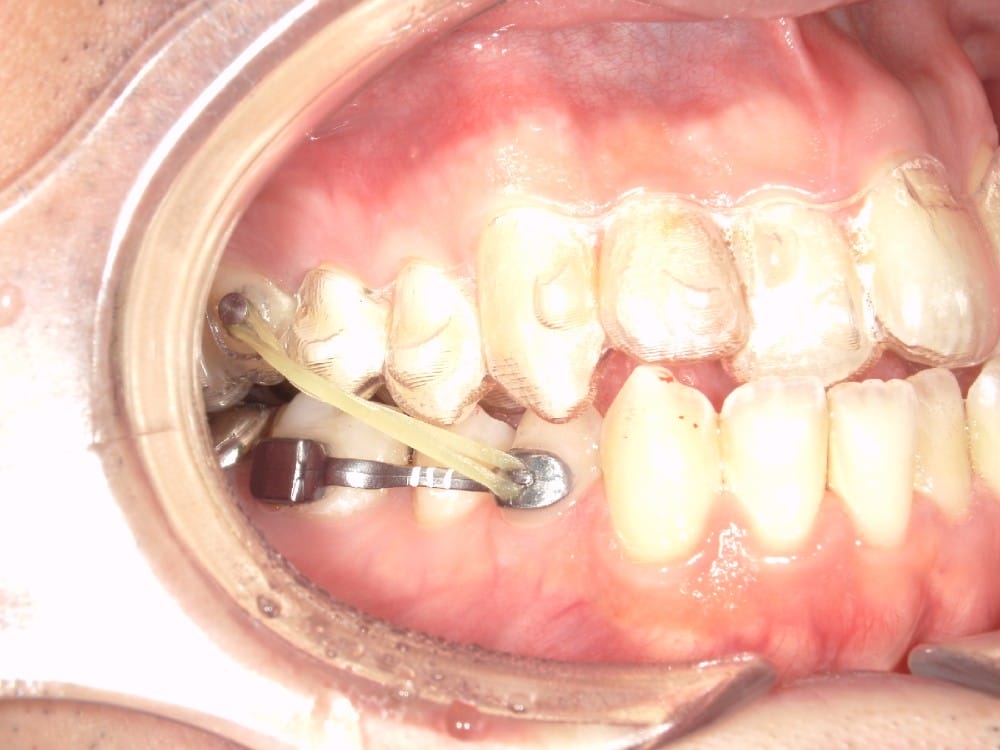

このような奥歯の移動量が大きい症例では、マウスピースだけでは難しいことがあり、カリエールとよばれる装置を補助的に使用し、上下の噛み合わせの前後関係を整えることで、手術を行わずに機能面と見た目の両方が改善することがあります。

一時的に前歯は噛み合わせが開いていますが、受け口の矯正では、最終段階で前歯ばっかりあたって奥歯がしっかり噛まないということも起こりやすいので、あえて狙って動かしています。

ここから上下透明なマウスピースに変え、仕上げていきました。